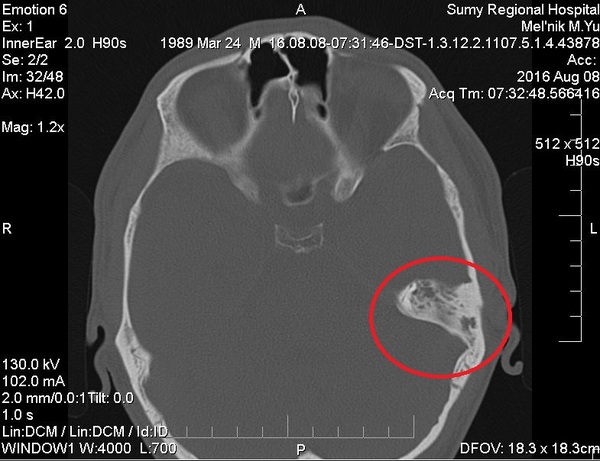

Прошло еще 3 года и две недели назад резко заболело ухо, причем очень сильно. Опять поездка, госпитализация, курс лечения (без оперативного вмешательства). Почему без операции? На этот раз все немножко хуже. Направляют в Харьков, так как у моего лечащего врача, к сожалению, нету необходимого оборудования (в том числе аппарата, просвечивающего лицевые нервы) поэтому максимум, что можно сделать - вычистить все с левой стороны, включая косточки, проводящие вибрацию звука. Деньги льются рекой, как шампанское на вечеринке после вручения оскара ДиКаприо. Сегодя/завтара выписывают и через пару недель на операцию в другой город. И да, эта херь сродни снаряду в голове. Никто не знает, когда оно может сдетонировать.

Что я хотел всей этой писаниной сказать? Ребята, берегите здоровье (уши в том числе). Проверяйтесь почаще у врачей. У толковых. При первом же "звоночке". И никогда не затягивайте. А лучше - вообще не болейте! :) Бонусом - мой снимок КТ: